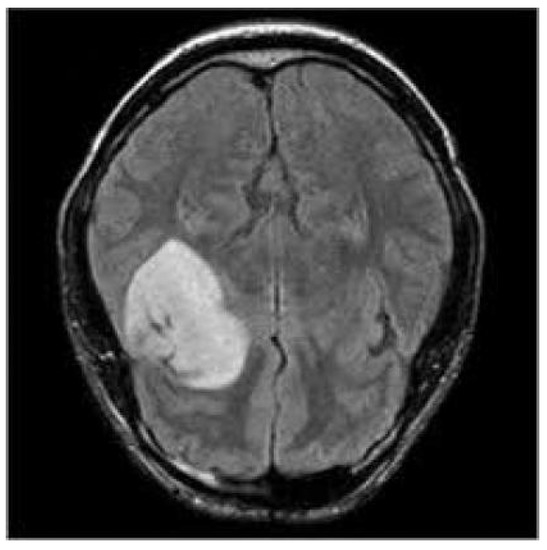

3.3. Prediction Examples